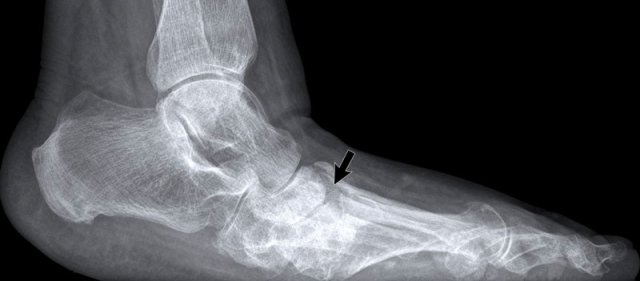

Hemophilic arthropathy of the ankle Hemophilic arthropathy of the ankle

Image of the ankle of a patient with hemophilia.

The findings are:

• extensive symmetrical joint space loss,

• subchondral bone cyst formation

• erosive changes

Hemophilic arthropathy Hemophilic arthropathy